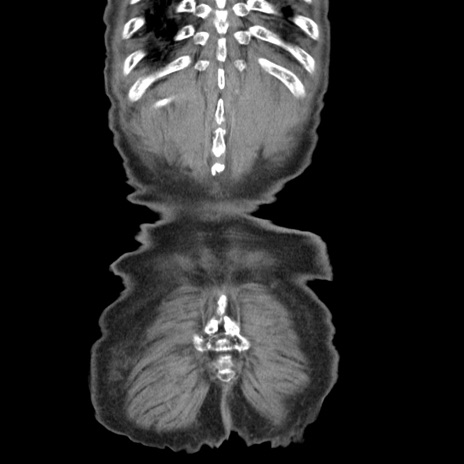

症例24(冠状断像)

矢状断像